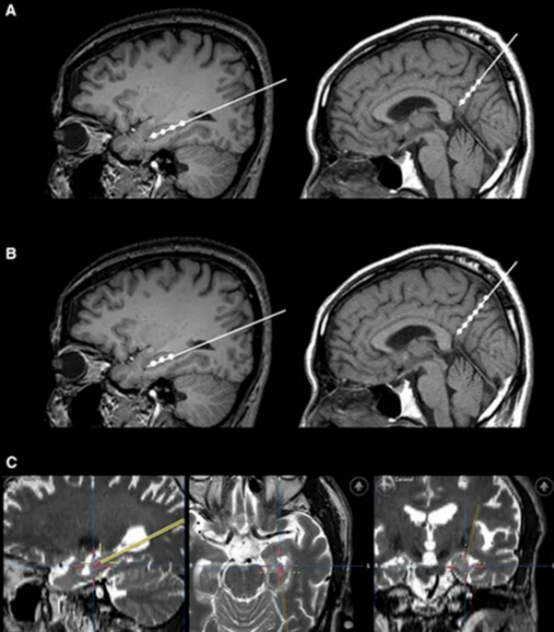

2015年《Alzheimer’s & Dementia》雜志曾報道,9例輕度至中度AD患者接受立體定向腦注射間充質(zhì)干細(xì)胞后,24個月隨訪中無1例出現(xiàn)嚴(yán)重不良反應(yīng),海馬體體積較治療前略有增加——這是傳統(tǒng)藥物從未實(shí)現(xiàn)的“腦體積保護(hù)”。